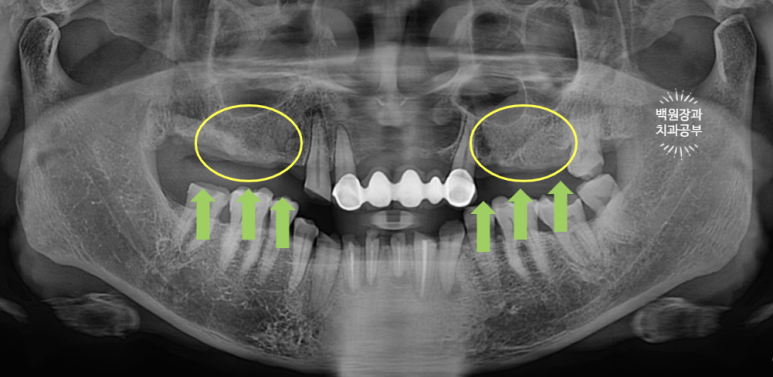

노란색 동그라미로 표시한 위턱 어금니는 당연히 틀니 혹은 임플란트로 만들어주어야 합니다.

환자분은 고정식 치료를 원하셨기 때문에, 위턱의 빈 자리에 전체 임플란트 수술을 계획하였습니다.

아래 어금니들은 위 어금니가 없는 사이에 너무 많이 정출되어 있었어요.

치아가 교합평면 (occlusal plain)을 기준으로 보았을 때 너무 튀어나왔기 때문에 깎아 내릴 필요가 있었어요.

(녹색 화살표로 표시해 둔 치아들은 3-4mm 이상 정출되어 있었어요. 대합치가 없기 때문이죠.)

다른 치과에서는 아래 어금니도 다 뽑고 임플란트를 하자고 하셨었는데, 치아들의 흔들거림이 없었기에 신경치료와 크라운치료로 아래 어금니들을 최대한 활용해보기로 계획했습니다.

정말 뿌리만 남았던 아래 앞니는 제거했습니다.